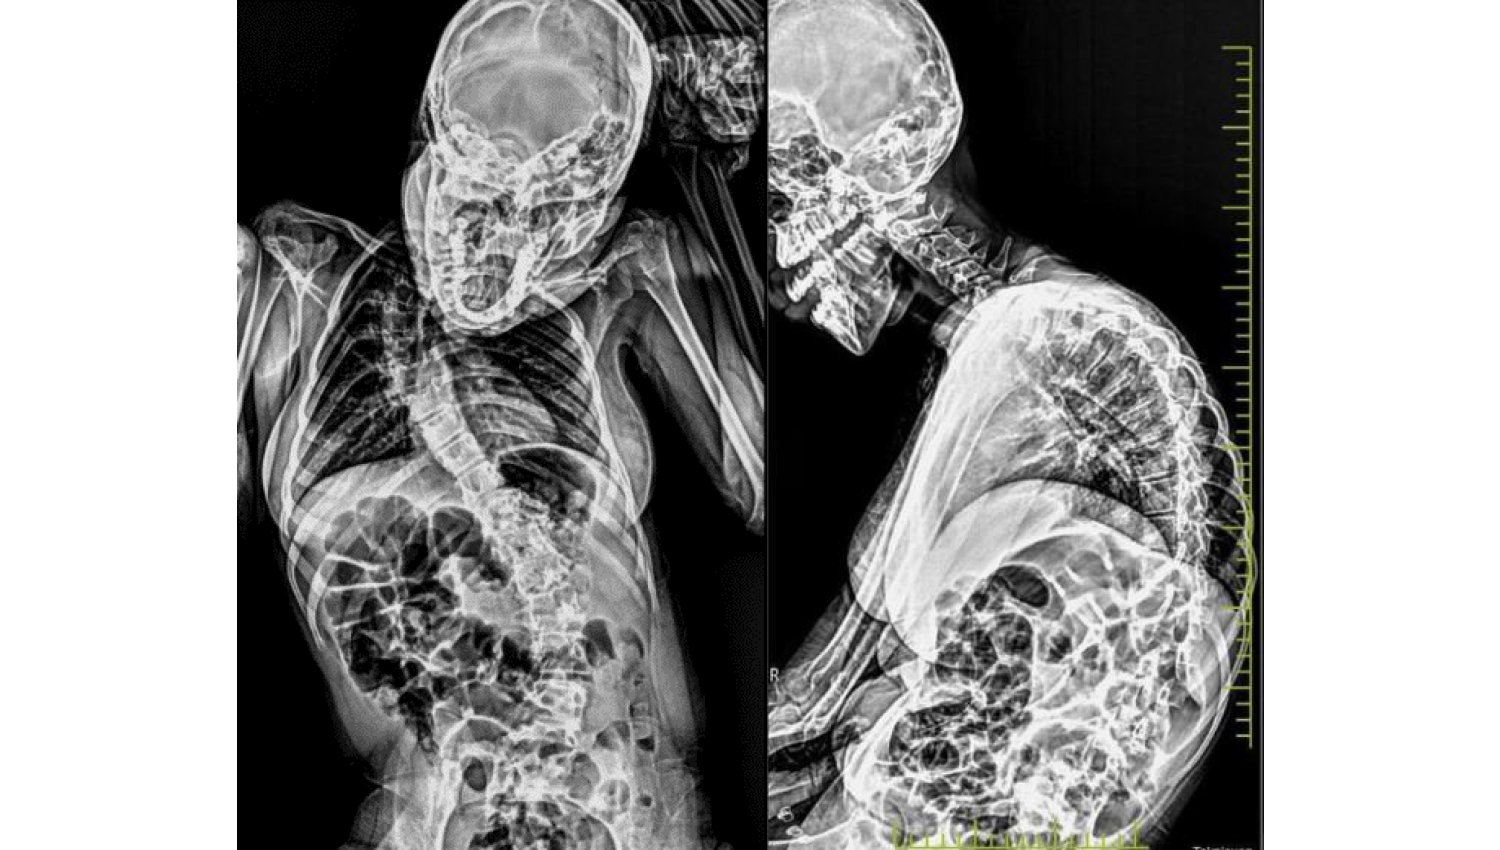

1.Initial radiological view.

4.Before and after radiological view.